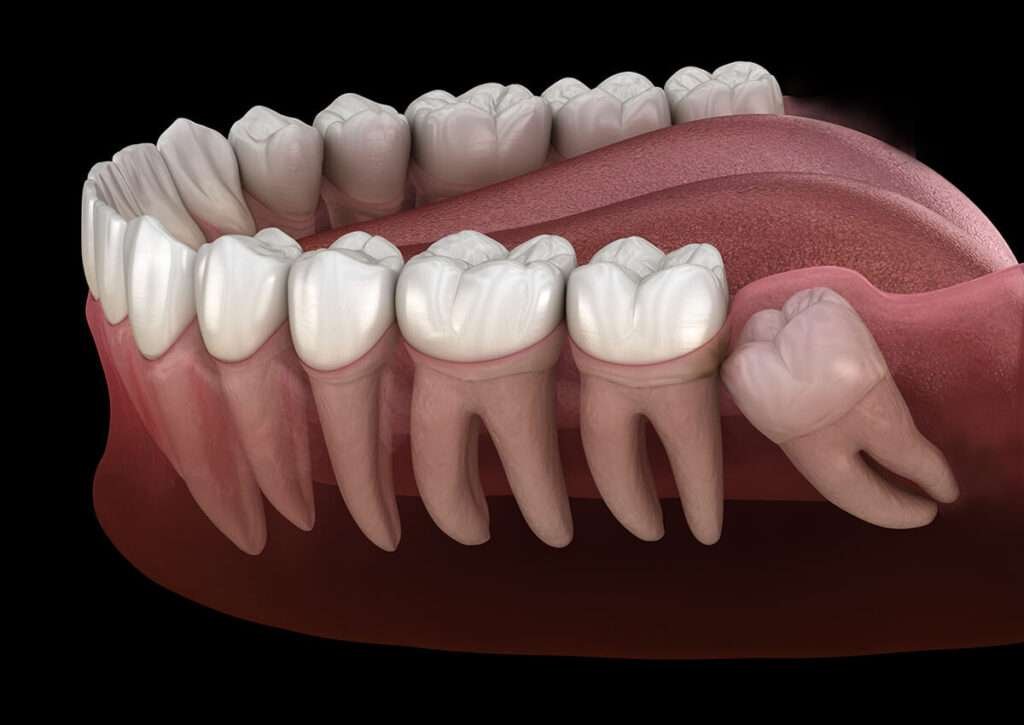

Wisdom teeth are the last set of molars that usually appear between the ages of 17 to 25. Due to limited jaw space, they often become impacted wisdom teeth, leading to pain and oral health issues.

- The tooth is impacted